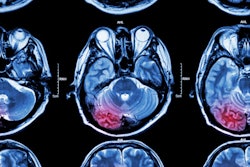

The combination of radiomics and a machine-learning algorithm can determine on CT if an ischemic stroke in the basal ganglia occurred within the window of time in which a stroke patient can still receive thrombolysis, according to research published online February 10 in the Journal of the Neurological Sciences.

About 40% of strokes originate in the basal ganglia, the most common site for ischemic stroke. Intravenous tissue plasminogen activator (tPA) is the main thrombolytic therapy for acute stroke, but it must be administered within 4.5 hours from when the onset of stroke symptoms is witnessed. Unfortunately, about 30% of patients can't receive tPA because they don't know when the stroke began -- even though it may actually have occurred within that time frame, according to the researchers.

Although CT is typically more readily available to patients than MRI, it can be challenging to estimate stroke onset time on these studies, according to the researchers. As a result, they sought to utilize radiomics to overcome these limitations.